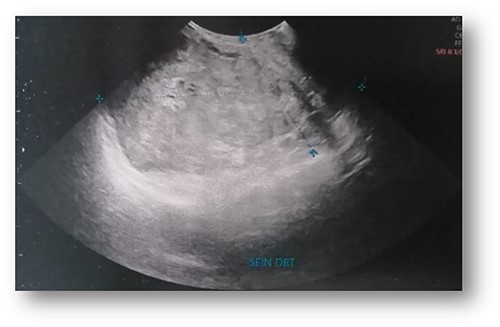

Ultrasonographic examination showed large heterogenous hypoechoic mass vascular on doppler with polylobed contours of 18 × 16 × 10 cm (Fig. 2). Mammography showed an enlarged right breast through the presence of a voluminous opacity with a focus of vermicular microcalcifications (Fig. 3). The lesion was graded BI-RADS score 5 (Breast Imaging-Reporting and Data System score—American College of Radiology).

Ultrasonographic examination: large heterogenous hypoechoic mass with polylobed contours of 18 × 16 × 10 cm.